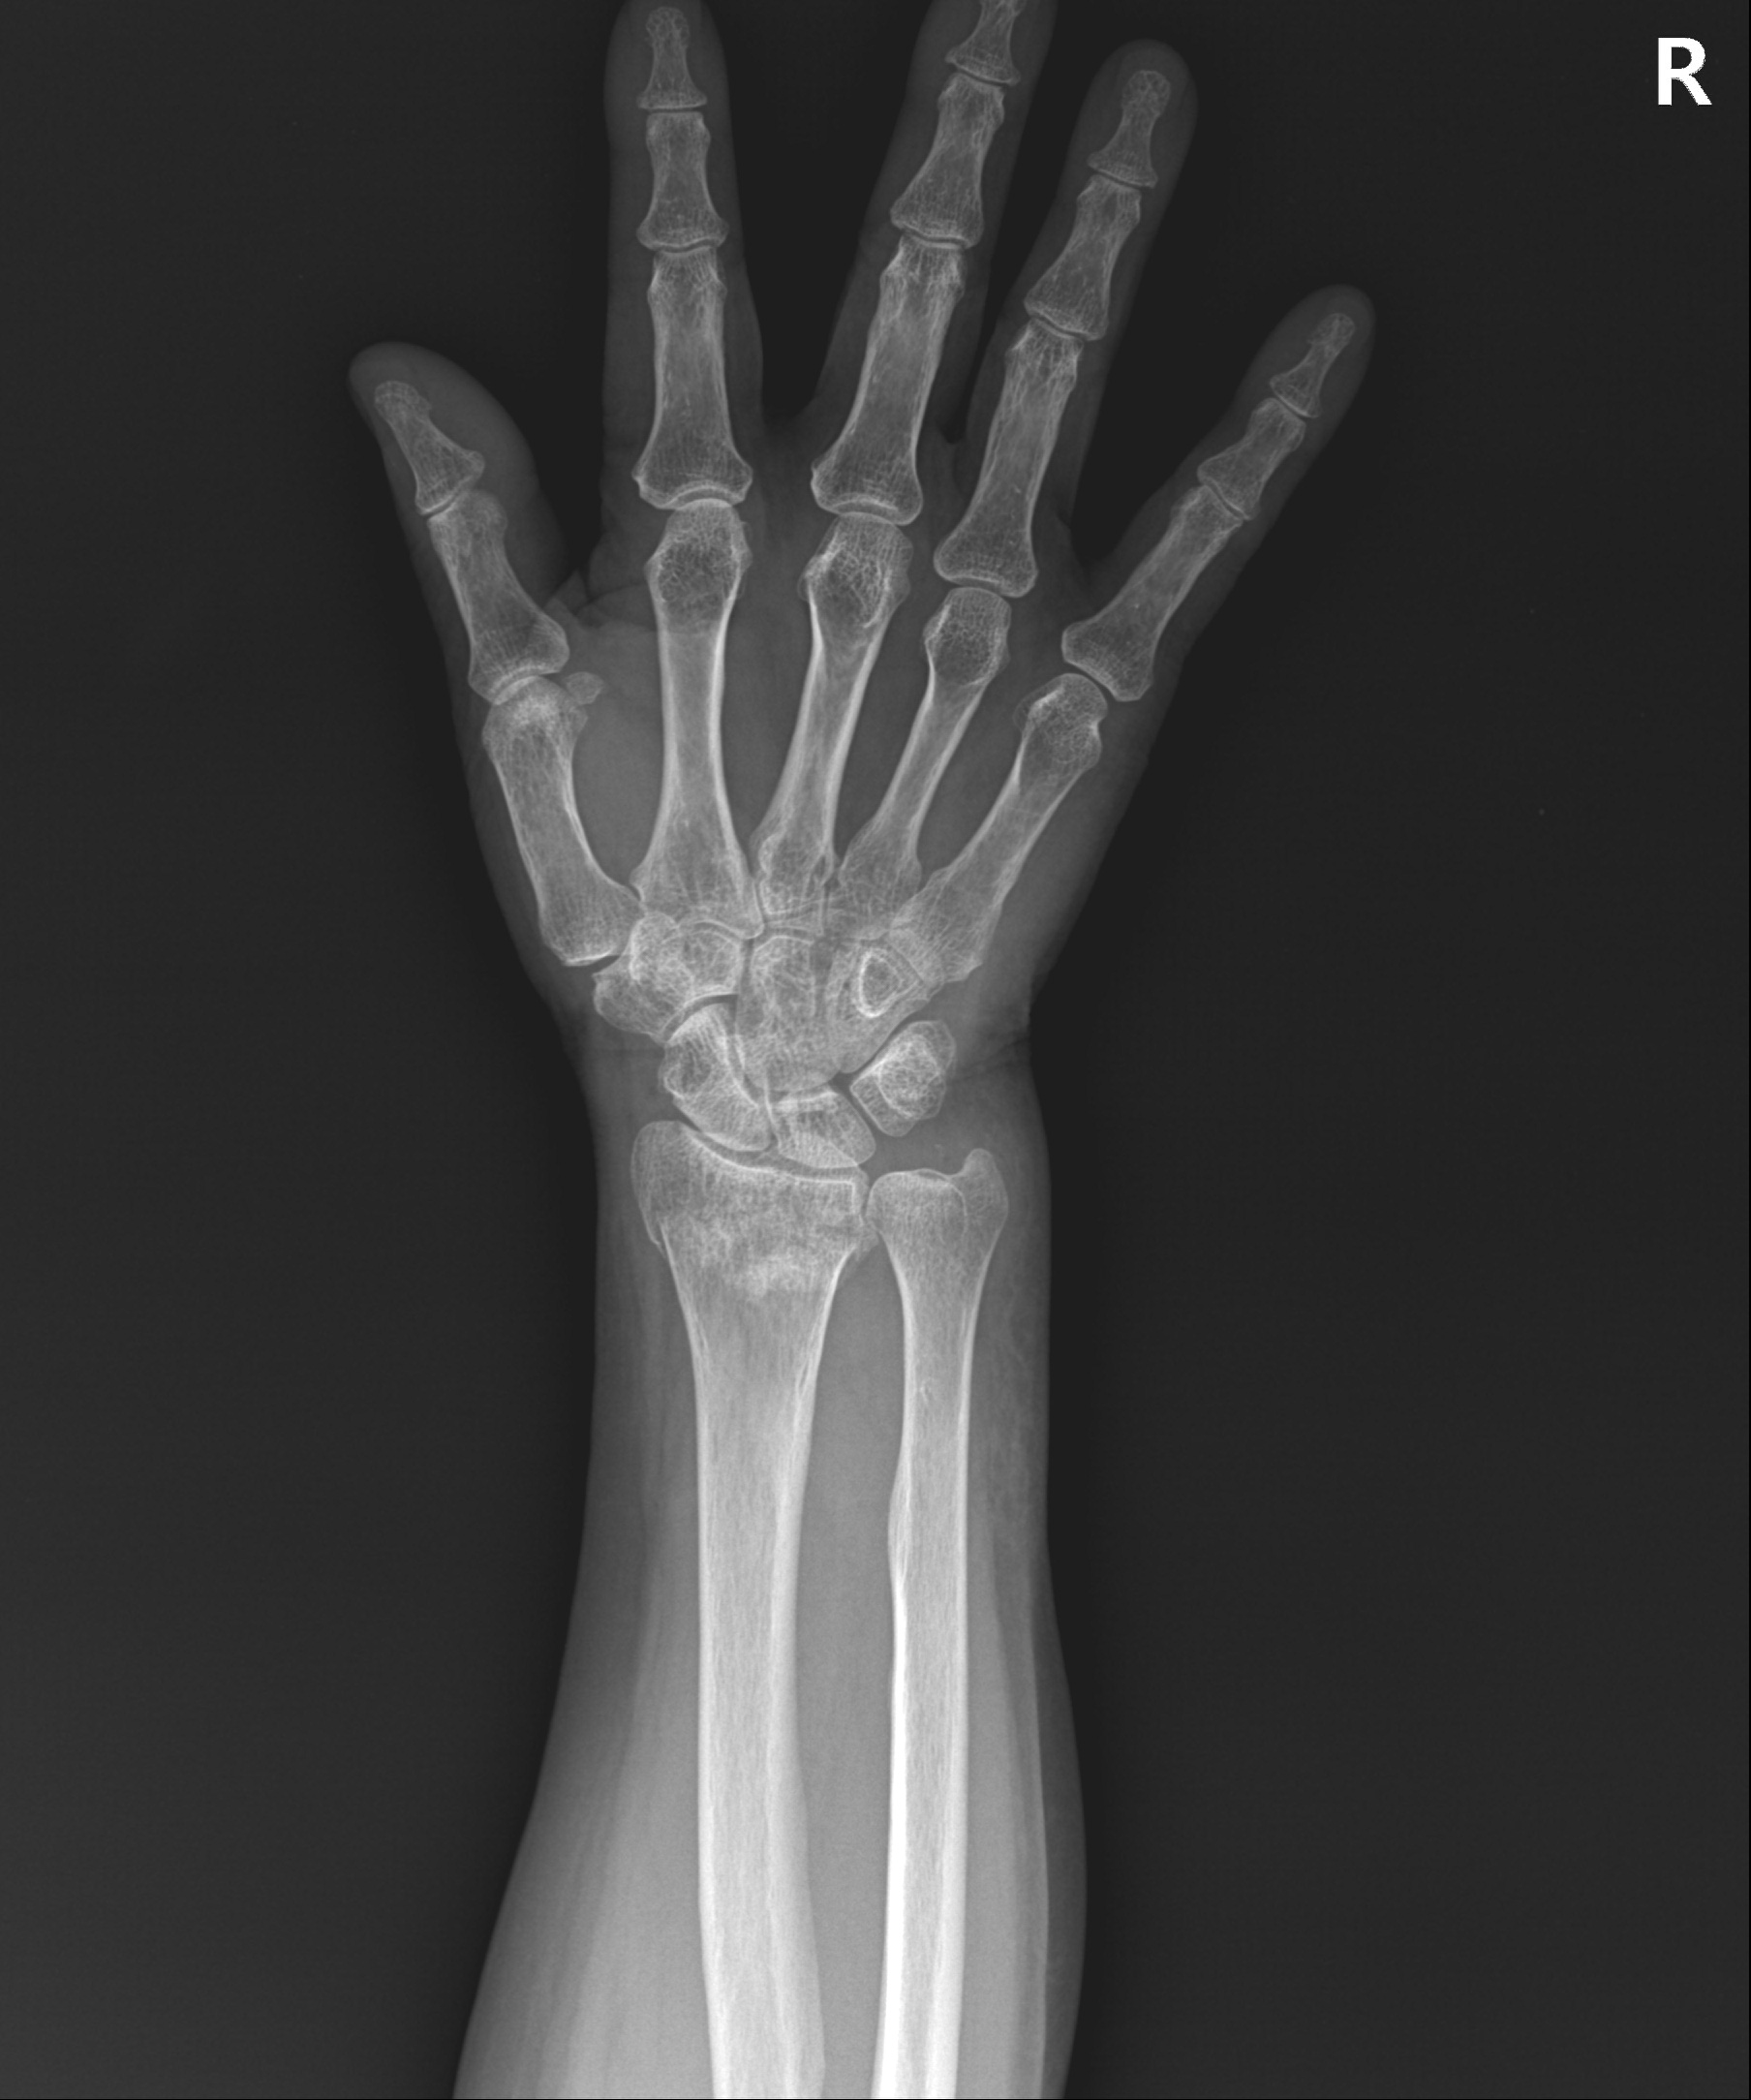

손목 골절 및 손가락 골절

대부분 손을 짚고 넘어지면서 발생하는 골절이고 다치면서 손등 쪽 뼈가 심하게 분쇄되는 경우가 많습니다.

골절 초기나 아니면 지연성으로 골절편이 손등 쪽으로 휘어져 변형이 발생하기 쉽습니다.

손목&손가락 골절에서 발생하는 문제점

□ 골절을 유합 시키기 위해 장기간 깁스를 할 경우 손목 관절이나 손가락 강직 발생

□ 손목 관절을 정확히 정복하지 못할 경우 외상성 관절염 발생 위험 높음

손목 골절

2023.01.04

2023.03.20